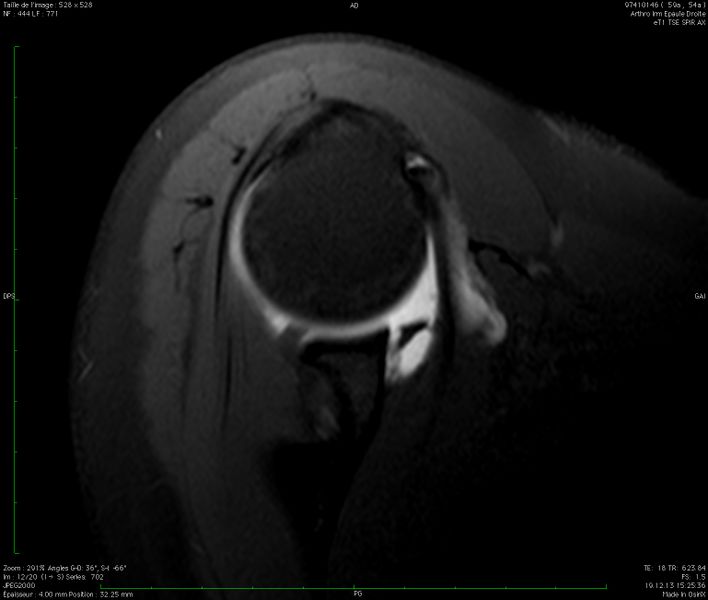

Coronal T1 SPIR magnetic resonance imaging (MRI) of a right shoulder showing disruption of the anteroinferior glenoid labrum. B